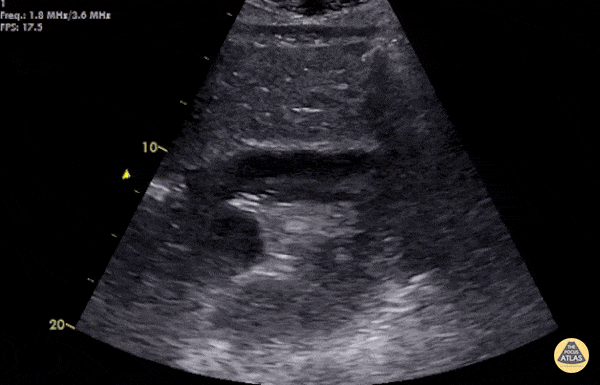

EA Echo Examples - Positive FAST - Tamponade

Young male with multiple praecordial stab wounds. Hypotensive and tachycardic with EMS. Haemopericardium with cardiac tamponade on subcostal window - taken to OR within 30 minutes of arrival. Clotted and fresh blood was evacuated from pericardial sac. Left internal mandatory artery and RVOT laceration repaired. POCUS images recorded by Dr. Deirdre Glynn and submitted by Dr. Cian McDermott - Dublin, Ireland